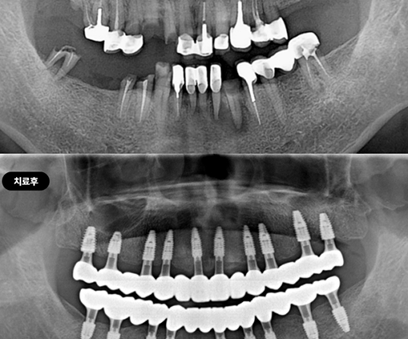

В нашей клинике используется цифровая система планирования, что позволяет точно спланировать место установки каждого импланта, минимизировать хирургическое вмешательство и сразу же установить индивидуальные протезы.

Сложные случаи: полная имплантация